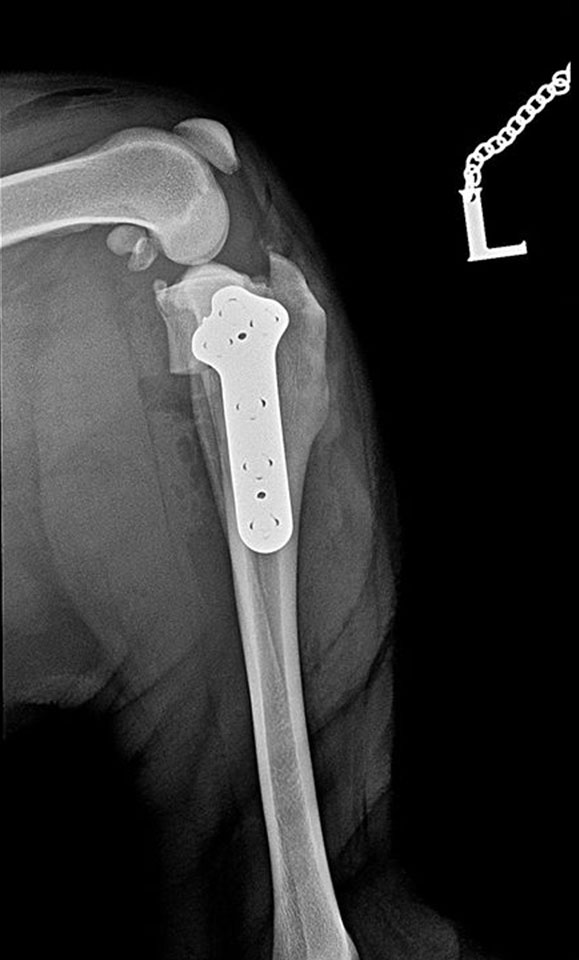

Shar-pei, cruciate ligament rupture surgery, TPLO with small pre-contoured polyaxial plate.

Sawed with R21 blade. Temporary fixation with 1,4 mm K-wire through the plate’s micro hole, which helps untill the locking poliax screws are driven in.